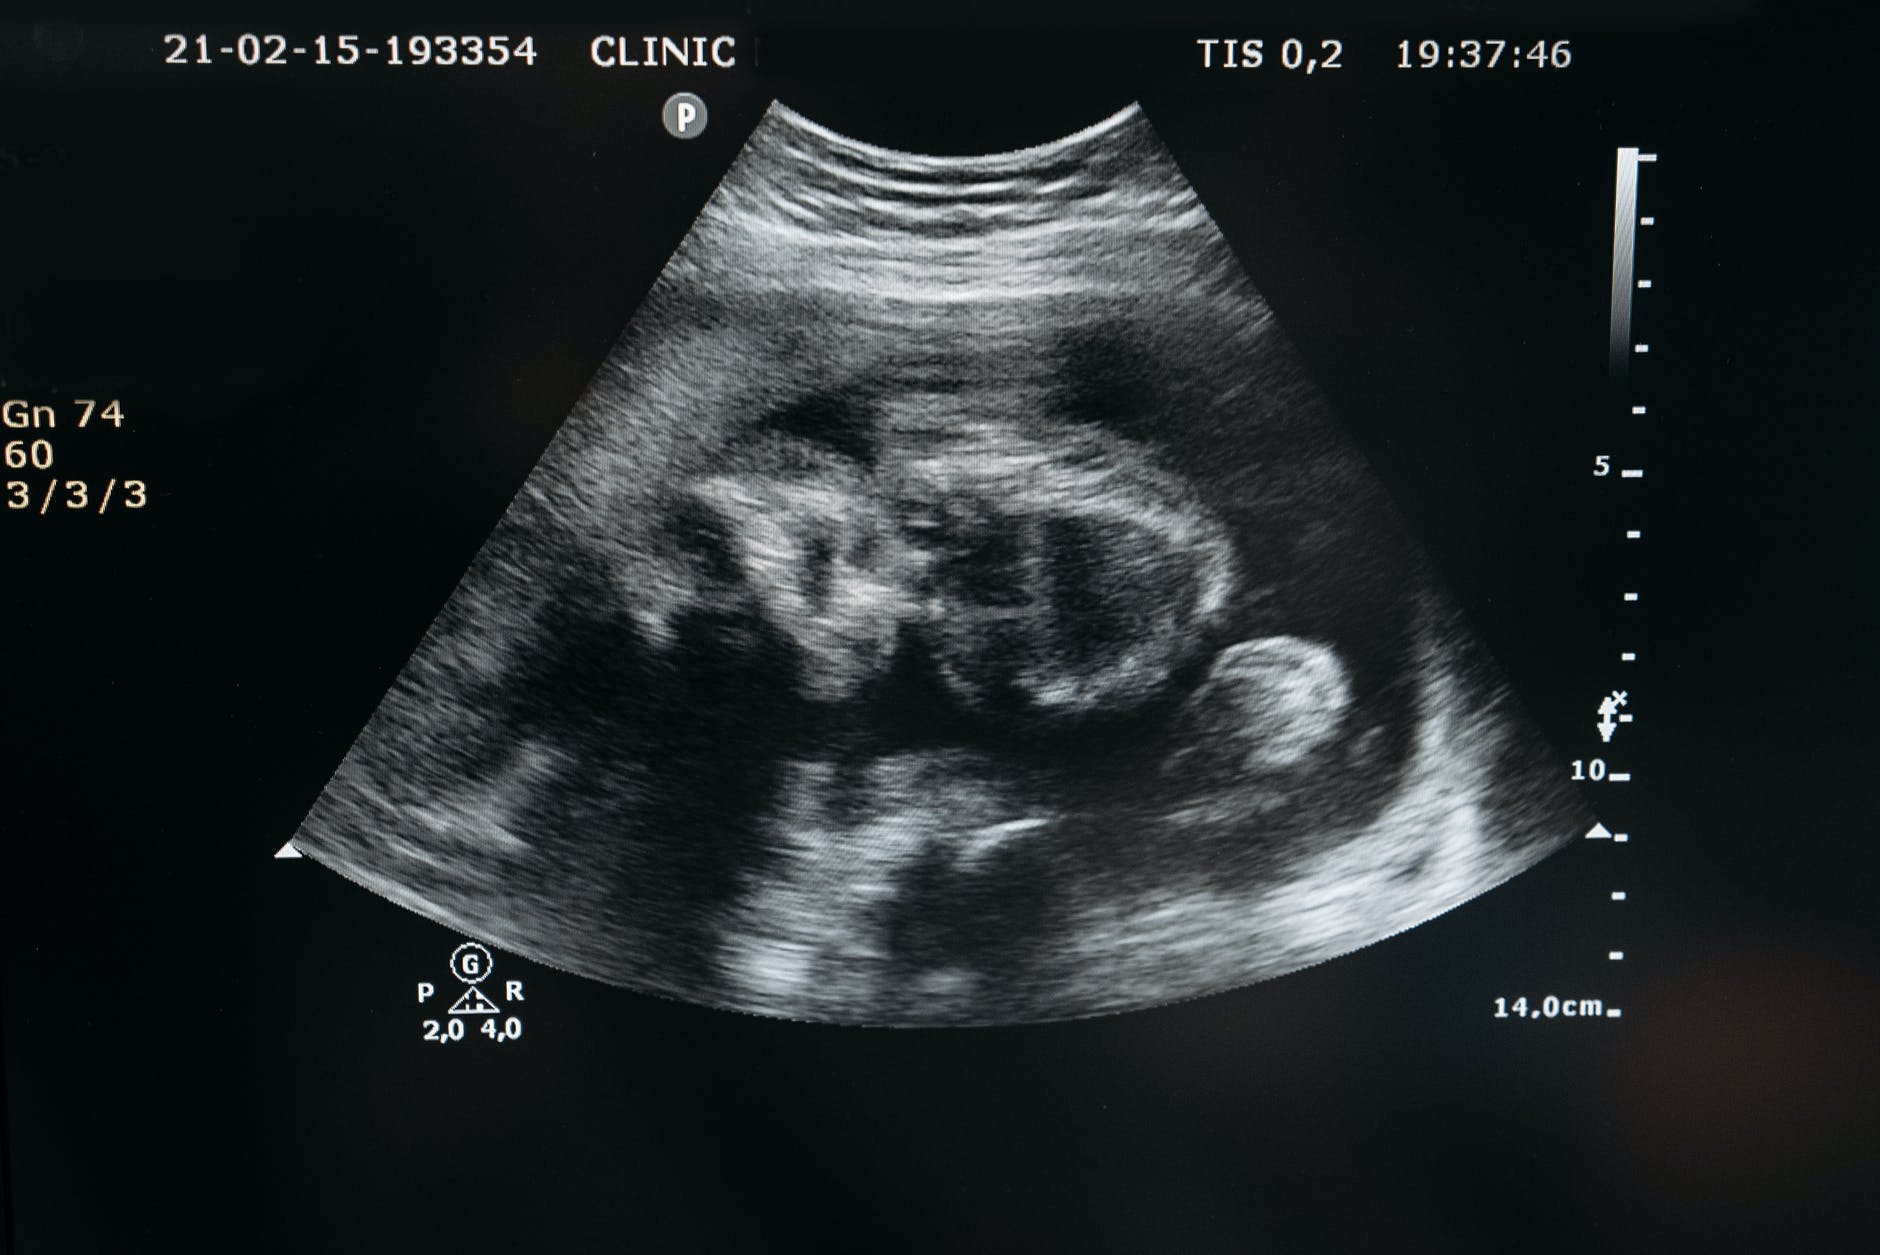

One of the arguments made by more extreme pro-choice versions is that since we cannot determine when personhood begins, then we are free to perform abortions into the third trimester without restrictions. Medical science tells us that by the third trimester this child is probably viable outside the womb. Also, just to look at it, this baby is remarkably full grown, is very actively moving, seems to have periods of activity and rest, and reacts to outside stimuli. Without resorting to a definition of personhood, this creature is a lot like us in many ways and deserves protection.